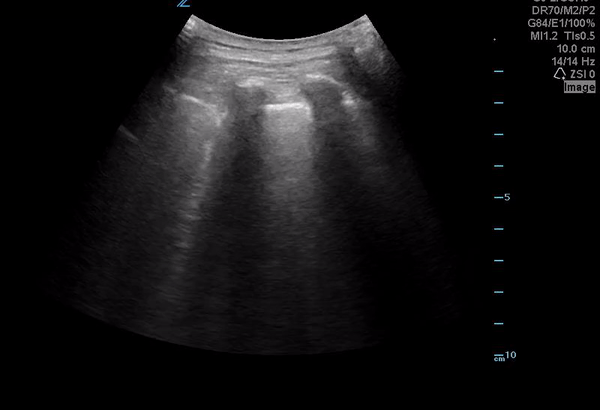

Scattered B lines-appreciated bilaterally

You notice the above pattern of B lines across the anterior precordium bilaterally. However at the lung bases you see the following.